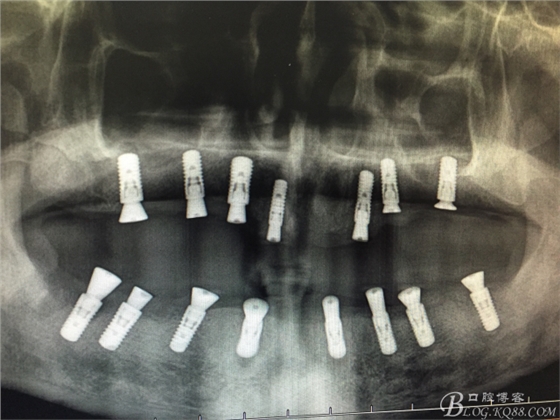

患者37歲 男 全口牙周病 手術(shù)一次完成 全程3小時全口種植修復(fù)全口種植修復(fù)全口種植修復(fù)全口種植修復(fù)全口種植修復(fù)全口種植修復(fù)全口種植修復(fù)全口種植修復(fù)全口種植修復(fù)全口種植修復(fù)全口種植修復(fù)全口種植修復(fù)全口種植修復(fù)全口種植修復(fù)全口種植修復(fù)